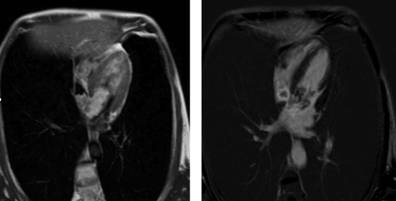

Due to the number of masses, the localization and the morphology of these, a cardiac magnetic resonance was performed, viewing one multi-lobed lesion hyperintense in T2, that compromised principally the left atrium and with lesser degree the right; in the dynamic sequences of early and late enhancement, there was a peripheral and patchy pattern uptake that persisted with capture defects in central nodular areas, findings that suggested as a primary diagnosis, a bi-auricular myxoma (Figure 3).

Figure 3: Cardiac magnetic resonance. To the left: mutilobed masses that compromise specially the right atrium and partially the left atrium, which are hyperintense on T2. To the right: peripheral and patchy enhancement of the contrast is observed and persists hypopcaptant in nodular central areas (characteristics of a myxoma).